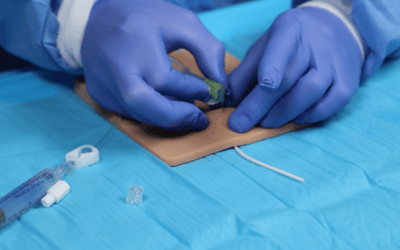

Conocer el comportamiento del ultrasonido en función de los tejidos atravesados es especialmente útil para evitar posibles errores de interpretación de la imagen y una mala elección del lugar de punción. Permite entender mejor qué está pasando en el momento del mapeo vascular pero también durante la inserción de la aguja en vena, lo cual conlleva a una mejor prevención del fracaso de colocación del acceso vascular.